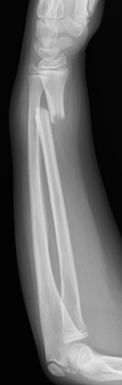

Las fracturas desplazadas o inestables precisarán de reducción cerrada o abierta en quirófano, asociado en algunos casos a osteosíntesis (Figura 10). Las fracturas localizadas en la unión metafiso-diafisaria distal son inestables y en muchos caos requieren tratamiento quirúrgico (Figura 11).

Figura 11: a, b-Fractura metafiso-diafisaria distal inestable. c, d-Control radiológico tras reducción donde se aprecia mala reducción. e, f-Síntesis mediante placa y tornillos.